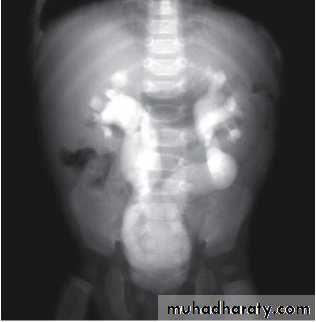

Grading of VUR

The degree of reflux is graded I–V.Grading is based on the appearance of contrast agent in the collecting system during voiding cystourethrography (VCUG(.

MCUG